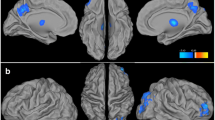

Large and significant differences in neurochemical levels were recorded when comparing age-matched RBT subjects to controls using non-parametric tests (P ≤0.05). Summarized in Table 3 and Figure 2 (scatterplot) are those cross peaks which are significantly different. Additional metabolites of interest such as NAA and mI (both have been shown to change in other traumatic brain injury (TBI) studies [23,24]) where changes were small or not statistically significant in this pilot series are also shown (Table 4).

Scatterplot of significantly different ( P ≤0.05) metabolites. The normalized cross peak areas, as measured in the posterior cingulate gyrus using L-COSY, of the different resonances of glutamate-glutamine (Glx-1,3,4,6), choline (Cho), fucosylated glycans and threonine and phenylalanine (Phe) are shown for RBT subjects in red boxes and age-matched controls in blue circles. For clarity, choline is plotted on a secondary y-axis (right) due to the difference in the values which is highlighted in blue. L-COSY, localized correlated spectroscopy; RBT, repetitive brain trauma.

The RBT cohort recorded an increase of 31%, 32% and 35% in the glutamine/glutamate cross peaks (2.09–3.75 ppm, 2.07–3.73 ppm and 2.14–3.74 ppm, respectively) (Table 3) when compared to controls. Figure 2 clearly demonstrates that for most of the Glx resonances there is no overlap between the RBT and control cohorts. It remains contentious as to whether glutamate and glutamine resonances are separable; thus, it cannot yet be ascertained if the increase is in glutamine or glutamate or both.

The methylene group of choline at 4.05–4.05 ppm was 65% higher in the RBT cohort. The scatterplot (Figure 2) shows that there is no overlap between the cross peak values measured in RBT subjects and controls. It is interesting to note that while the mean peak volumes of the choline resonances at 3.20–3.20 ppm and 3.51–4.05 ppm were greater, they were not statistically significant.

L-COSY also uniquely identifies additional resonances that cannot be characterized by one-dimensional MRS methods. For example, the cross peaks in the F2: 4.0–4.5, F1: 1.1–1.7 region, show a higher cross peak volume in molecules assigned to covalently linked terminal fucose molecules and threonine [21] of 60% in the RBT group [21]. The spectral region (F2: 4.0–4.5, F1: 1.1–1.7) contains threonine, fucose and, sometimes, lactate cross peaks. Originally assigned in the two-dimensional COSY from cultured cells [21,25] and more recently in vivo in the brain [11], these fucose cross peaks are also seen in the brain spectra reported by Velan et al. [14], but assigned to Thr/lactate alone. The assignment of bound fucose in the two-dimensional MR spectra was previously made using in vitro models by treating the cultured cells with fucosyl transferase and observing the bound cross peaks disappear and free α fucose at 1.22–4.21 ppm and free β fucose at 1.26–3.81 ppm appear [25]. It is the unique conformation of each of these terminal fucosylated species on the oligosaccharide chain on the cell membrane that generates the different chemical shifts for each fucose. Replicating this in a phantom is, thus, not possible [26].